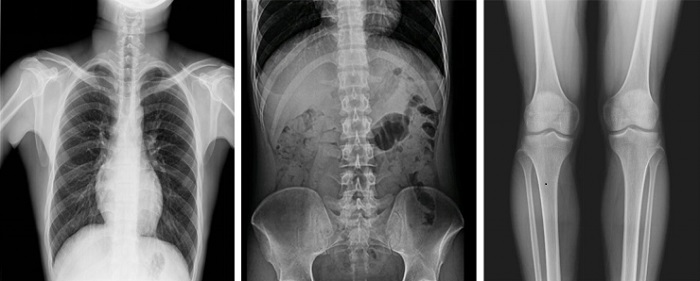

以普利德多功能動(dòng)態(tài)平板DRF為例,一改傳統(tǒng)DR只能進(jìn)行盲拍的模式,通過(guò)多角度動(dòng)態(tài)實(shí)時(shí)影像實(shí)現(xiàn)全方位觀察,當(dāng)疑似病灶出現(xiàn)時(shí),進(jìn)行瞬時(shí)高清點(diǎn)片,精準(zhǔn)捕獲高清病灶圖,大大降低漏診誤診率。同時(shí),17×17英寸大幅面成像,能對(duì)胸部、腹部等部位實(shí)現(xiàn)大范圍全覆蓋,更便于醫(yī)生觀察和診斷。